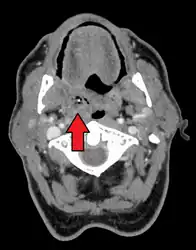

Diagnosis is usually based on the symptoms.[1] Medical imaging may be done to rule out complications.[1] Medical imaging may include CT scan, MRI, or ultrasound is also useful in diagnosis.[1]

Peritonsillar abscess on the person's right as seen on CT imaging